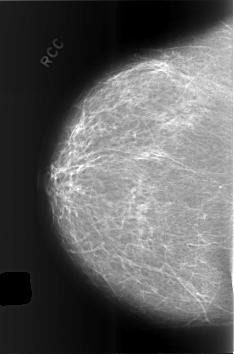

C_0496_1.RIGHT_CC

RIGHT_CC LINES 5656 PIXELS_PER_LINE 3744 BITS_PER_PIXEL 12 RESOLUTION 50 NON_OVERLAY